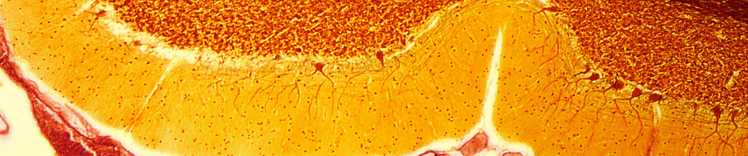

CÉLULAS DE PURKINJE EN EL CEREBELO

Cambios en el cerebro que envejece

Los cambios físicos en el cerebro asociados con el envejecimiento incluyen:

- Atrofia (contracción) tisular en algunas regiones

- Volumen ventricular aumentado

- Pérdida de neuronas y sinapsis y reducción de la formación de nuevas neuronas

- Acumulación de proteínas anormales